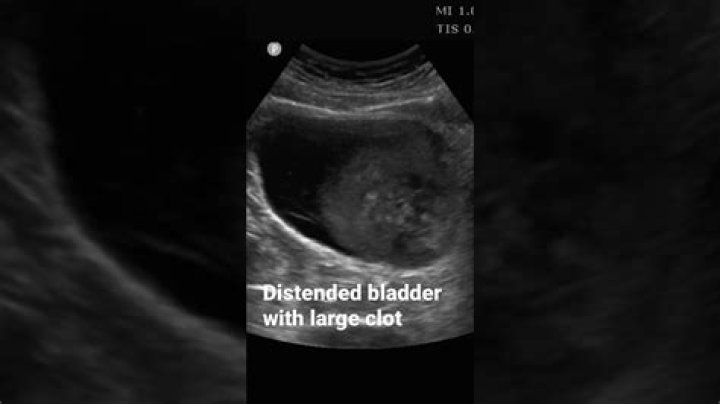

Why is my bladder distended

Usually the bladder walls become thicker and then grow because they are overstretched. The condition is sometimes referred to by medical professionals as bladder hypertrophy. An enlarged bladder can be present from birth or it can occur due to an obstruction in the bladder, the kidneys, or the connecting ureters.

What does having a distended bladder mean?

Term used to refer to urinary retention in the bladder due to its incapacity to void normally. It may occur because there is an obstruction or a loss of tone in the bladder muscles that fail to detect increased pressure exerted by urine. It is usually associated with pain and urge to urinate.

On abdominal examination, a distended bladder is palpated as a suprapubic fullness with dullness to percussion. A rectal examination with assessment of prostate size is also necessary. Look for abnormal laboratory findings such as worsening kidney function, hematuria, leukouria, or bacteriuria.